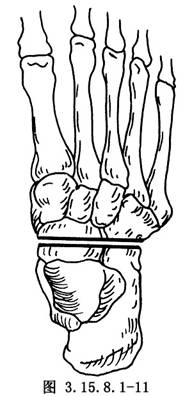

6.5.3 3.截骨矫形

先用骨刀截除跟骰关节和距舟关节,楔形截骨基底在背外侧纠正内翻畸形(图3.15.8.1-8),切除角度等于X线片第2趾和足中线形成的角度(图3.15.8.1-9)。若纠正足外翻畸形,楔形截骨基底可设计在内侧(图3.15.8.1-10),由于距舟关节和跟骰关节在一个平面上,切除角度是一致的(图3.15.8.1-11)。最后切除距下关节,纠正跟骨内收(图3.15.8.1-12),根据X线片胫骨中线和跟骨中线形成的角度,做外侧楔形切除(图3.15.8.1-13)。当骨刀切到对侧时,注意轻缓,尤其纠正外翻时,更要注意防止误伤胫后的血管及神经(图3.15.8.1-14)。将已切除的骨面合拢,如畸形纠正,骨面能紧密对合(图3.15.8.1-15),周围空隙植入切除多余的松质骨。